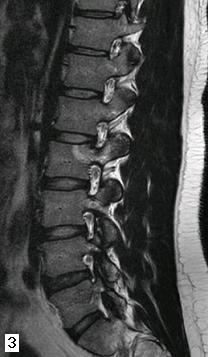

Figure 2a e 2b - La scansione TC sul piano trasversale (fig. 2a) e la ricostruzione su quello sagittale (fig. 2b) dimostrano il corretto posizionamento dell'agoelettrodo (22G). Dopo 10 ore dalla termoablazione il paziente non ha più accusato il tipico dolore da osteoma osteoide.

Figura 3 - Il controllo con RM, eseguito dopo 15 mesi dalla procedura, non fa più apprezzare l'osteoma osteoide; le strutture foraminali sono indenni; sono ancora presenti modesti fenomeni riparativi nella sede della termoablazione.